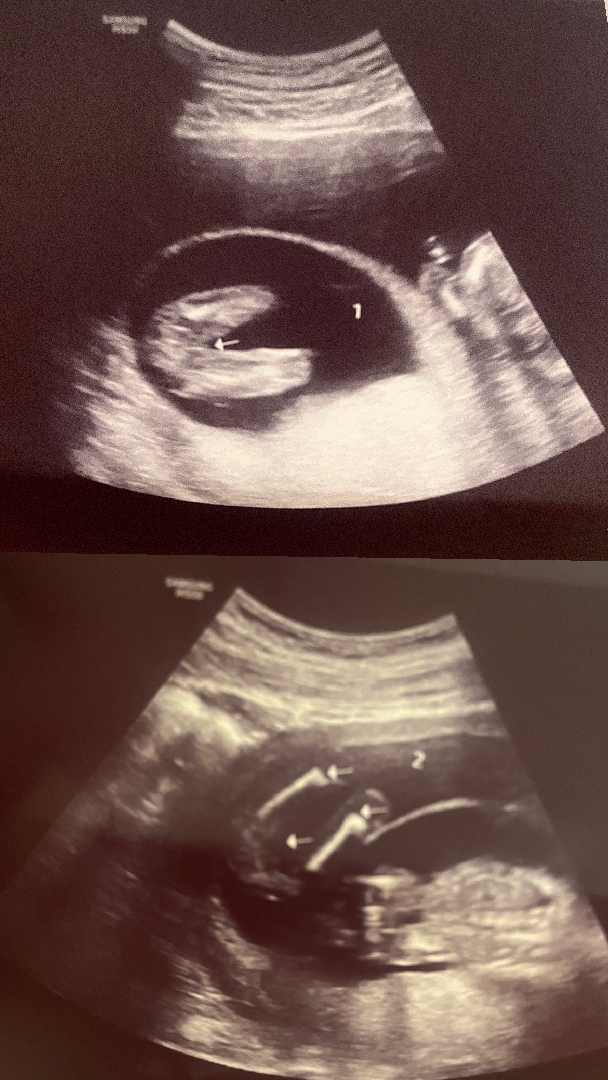

16주 2일 쌍둥이 성별 알려주세요!!

방금 둥이 아가들 성별 확인하려고 초음파 보고 왔는데 화질이 좀 안좋아서 그런지 확답을 못받고 왔네요. 16주 2일 되었는데 쌍둥이 둘다 17주 0일만큼 컸다고 해서 기대했는데 성별 판별 잘하시는 전문가님들 의견을 기다립니다!!

딸같아요

첫번째 초음파는 딸같구 두번째는 잘 보이지는 않지만 딸같은 느낌이 있어요